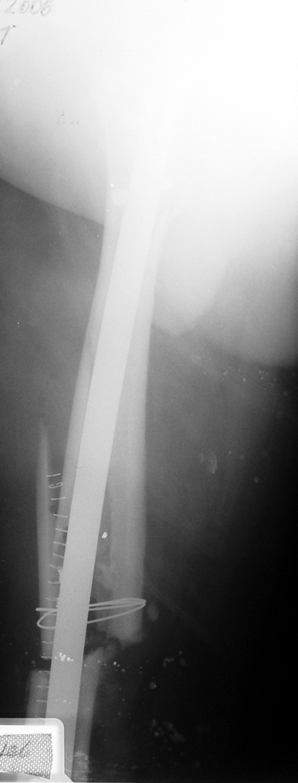

Vaka 3